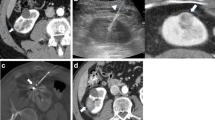

Display detail of the surrounding area of the single-needle bipolar probe during digital substraction angiography (DSA) while performing NTIRE to the lower part of the isolated perfused porcine kidney. The open black arrows show the fluctuation of the X-ray contrast agent based on the apex and the basis of the nonisolated lower pole of the NTIRE single-needle electrode (see Fig. 2)

Marker and Digital Angiography in Mammography Technique (Static Angiography)

Directly afterwards each kidney was perfused with NaCl 0.9% (4°C) again until the iodine contrast agent for DSA was cleared out. Accordingly the kidneys were perfused with barium sulphate contrast agent (Barilux® HD, Sanochemia, Switzerland) into the renal artery until draining it off the renal vein. Then, the arterial, venous, and ureteral tubes were closed to keep the intravascular and nondiffusible contrast agent inside. Subsequently digital static angiography was performed by mammography technique with 50 cm, 24 kV (low-kV exposure technique, high resolution) and 80 mAs (Mammomat 3000®, Siemens, Germany). Each X-ray image (whole kidney and its 5-mm coronary transactions; Figs. 4, 5) was observed by two independent and experienced interventional radiologists and two independent and experienced urologists in consensus.

Images of the half-split kidney (left) and correspondent digital static angiography per high-resolution X-ray imaging in low-kV exposure mammography technique (right). Open arrows show a small pre-existing cortical cyst. Closed arrows show the metal markers set to the NTIRE electrode channels (3 per kidney)

Digital static angiography per high-resolution X-ray imaging in low-kV exposure mammography technique of the coronary kidney transactions display detailed the renal vascular system around the metal markers (upper pole to the left, central zone in the middle, lower pole to the right). Each metal marker shows one of the NTIRE puncturing channels

Before NTIRE, we observed regular and physiological perfusion with flooding and complete draining off the vascular system of the renal parenchyma without any perfusion gaps. During (Figs. 2, 3) and after (Figs. 4, 5) NTIRE, we observed no relevant changes, such as extravasations, perfusion gaps, open areas, accumulations, or stases in the renal parenchyma. Conspicuous was a concentric wavelike fluctuation of the contrast agent, each based on the apex and basis of the nonisolated lower pole of the NTIRE single-needle bipolar probe, which appeared simultaneous to the NTIRE pulses (90/min), expanded around 1 cm and cleared away completely during perfusion (Fig. 3).

Digital Angiography in Mammography Technique (Static Angiography)

The correlation of the NTIRE ablation zone to the angiography images was feasible by marking the NTIRE puncture channels per metal marker (Figs. 4, 5, closed arrows). The contrast agent stayed characteristically intraluminal of the complete organ. In correlation to the marked ablation zones, we observed no extravasation and no disruption of the terminal vascular bed of renal cortical parenchyma, such as gaps, open areas, or accumulations—neither around the seeds nor in the distant parenchyma (Figs. 4, 5). Additional to the DSA, also small vessels of the renal cortex are displayed straight to the renal capsule and can be well distinguished from each other (Fig. 5). In the following these small vessels, which are not detailed visible in DSA, are defined as microvascular system of the kidney.

This experimental study is the first radiological approach to examine the renal vascular system in the acute phase of NTIRE. Conventional DSA before, during, and after NTIRE as well as digital static angiography per high resolution X-ray imaging in low-kV exposure mammography technique after NTIRE were used in isolated, perfused, porcine, ex vivo kidneys. This enables a qualitative radiological examination of the NTIRE ablation zone closed and surrounded terminal macro- and microvascular bed of renal parenchyma in the acute phase. Referred to its typical anatomy of the renal vascular system, the DSA shows the renal macrovascular system with vasa renales, segmentales, interlobares, and arcuatae of the renal medulla and columns (Fig. 2), whereas the angiography in mammography technique additionally shows the renal microvascular system with vasa corticales, rectae spuriae, and rectae verae of the renal cortex and pyramids (Figs. 4, 5).